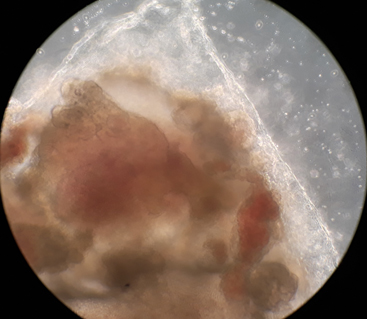

My mini-brain under the microscope.

I should be very clear what this term “mini-brain” implies. Some researchers reject it, and I see their point. Human neurons grown in a cell culture in this way can’t make a brain, not even in its early fetal form. But these nerve cells do start to create, under the direction of their own genetic programme, some of the features that a real developing brain exhibits. They become specialized into some of the many different cell types – not just neurons – that are found in our mature brains. And they acquire some of the anatomical structure of brains: the well-defined layers of neurons seen in the cortex, the folds and convolutions of the tissues. It’s rather like a very young child’s drawing of a person: not much of a resemblance really, but you can see what they’re getting at. You can see the potential to do a better job. A more neutral term for these lab-grown cell structures is “organoid”: the cells construct something that looks like a crude representation of an organ of the body, reduced in scale. It is possible to grow organoids resembling livers, kidneys, retinas, gut, as well as brains – all in a dish, outside the body. I want to ask what this means, for medicine, fundamental biology, philosophy and our sense of identity.